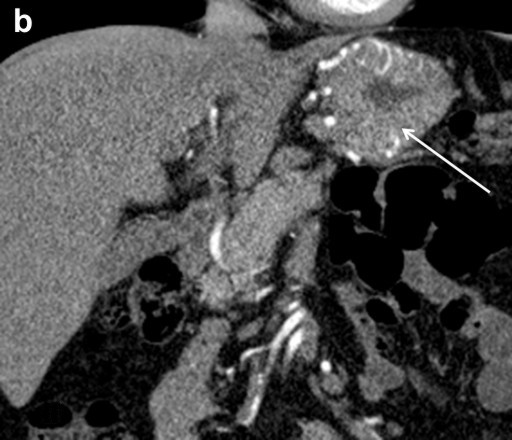

Preceding surgery, the splenic artery was always seen on CT angiography as a thick stem with no other branches travelling to the spleen (Figures 7a and 8a). As a consequence of splenic artery resection, the whole or the bulk of its trunk were no longer available for evaluation by CT angiography after a spleen-preserving distal pancreatectomy with resection of the splenic vessels and, in all 10 cases, the gastroepiploic arcade was seen to have become the “highway” to the spleen within 7-30 days after surgery (Figures 7b, 8b, and 9). In two cases, due to technical reasons, 3D CT angiography was only carried out postoperatively but, in both cases, there were no doubts about the source of the blood supply to the spleen (Figure 9). In none of the 10 cases was any appreciable blood flow through the short gastric arteries visualized.

Figure 8. Celiaco-mesenterial anatomy in а 59-year-old woman with a neuroendocrine tumor of the pancreatic body and tail. 3D CT angiography after the renal artery images were eliminated. a. Before surgery: the splenic artery thick trunk with no collaterals is shown. b. Ten days after a spleen-sparing distal pancreatectomy with resection of the splenic vessels: the spleen is fed through the gastroepiploic arcade. There are no other detectable major arteries to feed the spleen. c. After surgery, vertical view: the arrow is pointing to the gastroduodenal artery, i.e., the site of origin of the gastroepiploic arcade. GEA: gastroepiploic arcade; LGEA: left gastroepiploic artery; SA: splenic artery |